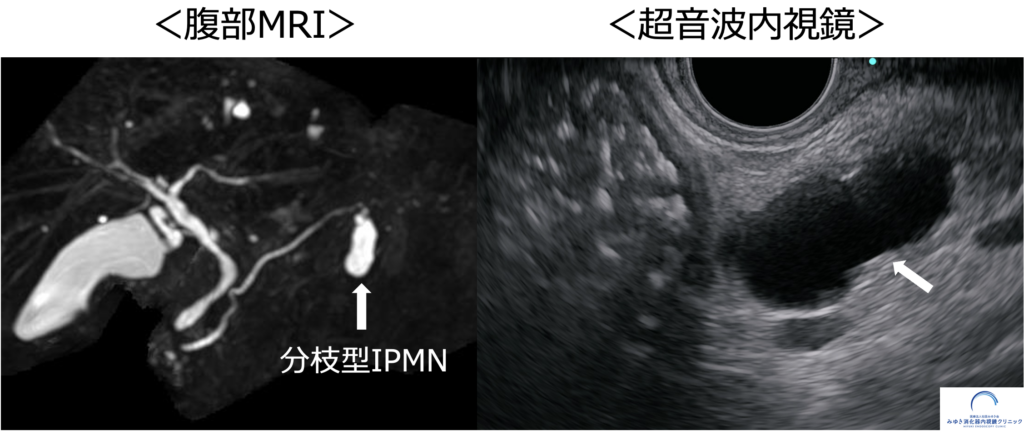

腹部MRIと超音波内視鏡(EUS)で観察された分枝型膵管内乳頭粘液性腫瘍(IPMN)